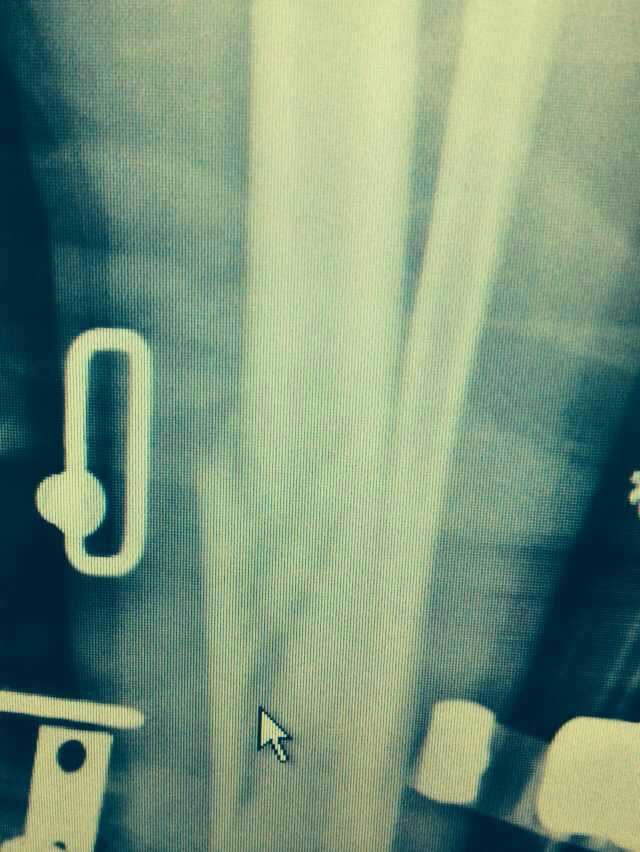

【byb.cn 】(來(lái)源:綜合)2014年12月18日,現(xiàn)年57歲的著名體育評(píng)論員韓喬生,在崇禮云頂滑雪場(chǎng),騎行德國(guó)雪上自行車的時(shí)候,因速度太快,控制不住,韓喬生為避免沖下路基,與一滑行單板的美女相撞,美女因裝備厚,無(wú)大礙,韓喬生則導(dǎo)致左腿脛骨、腓骨兩外骨折,后已經(jīng)被緊急送往北京的醫(yī)院治療。